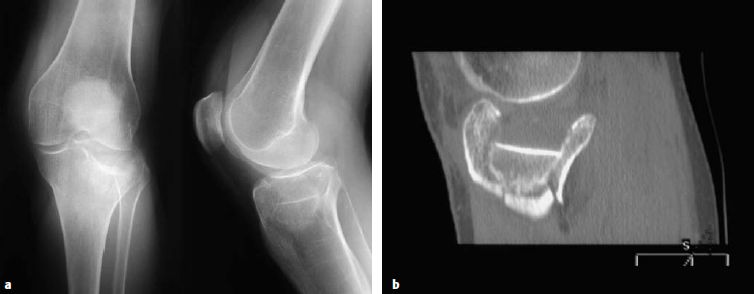

术前CT扫描提供的多个切面以及三维重建已经成为胫骨平台骨折分析的标准工具。CT扫描的时机尽可能选择在进行初始复位并通过石膏或者跨关节外固定架固定后。随着CT技术的发展,骨折的位置及其累及的“柱”受到了越来越多的关注(图6.8.1‑2),有时由于骨折的位置的关系,其损伤范围在X线上难以发现。

图6.8.1-2

后外侧胫骨平台骨折的X线片(a),骨折形态不如CT的轴位(b), 冠状位(c)和三维重建(d)那么清楚。